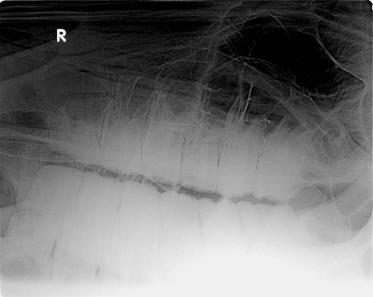

Klinisch sind zwei offene Pulpen an dem zweiten oberen Backenzahn zu sehen. Das Röntgenbild zeigt eine deutliche Aufhellung um eine Wurzelspitze des betroffenen Zahnes. Die Pulpitis hat sich bereits im Kieferbereich manifestiert. Die vorausgegangene Röntgenuntersuchung vor 7 Monaten hat diesen Befund im Kiefer noch nicht gezeigt.

Sorgfältig wird die Wundhöhle optisch per Spiegel und fühlend mit der Hand inspiziert, ob alle Zahnsplitter restlos entfernt wurden. Ein Röntgenbild bestätigt dies zudem im Anschluss.